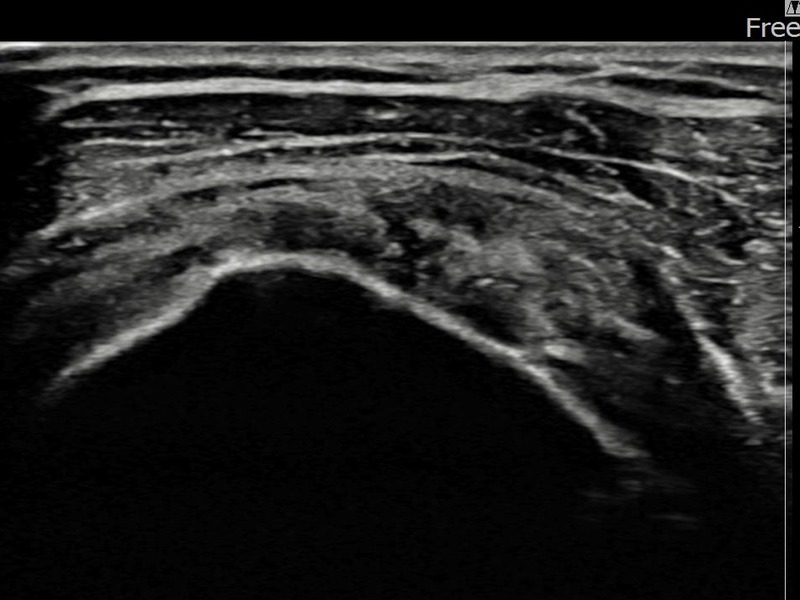

정ㅇㅇ님 · 좌측 극상근건 부분파열

좌측 어깨 통증이 오래 지속되어 내원하셨습니다. 초음파 검사에서 극상근건 부분파열이 확인되었으며, 어깨인대 축소봉합술 시행 후 장기 추적 초음파에서 힘줄 연속성이 완전히 회복된 것이 확인되었습니다.